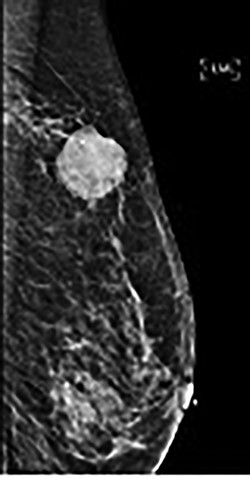

Physical examination yielded a 2-cm well-circumscribed, mobile, non-fixed, palpable mass in the upper outer quadrant of the left breast. She had no axillary lymphadenopathy, nipple retraction, excoriation, drainage or radiation-induced skin changes. Mammography and ultrasound of the breast mass demonstrated a 1.3 × 1.2 × 1.3-cm echogenic mass with irregular margins and posterior enhancement (Fig. 1). Core needle biopsy demonstrated adenocarcinoma that was morphologically identical to the patient’s known parotid malignancy.